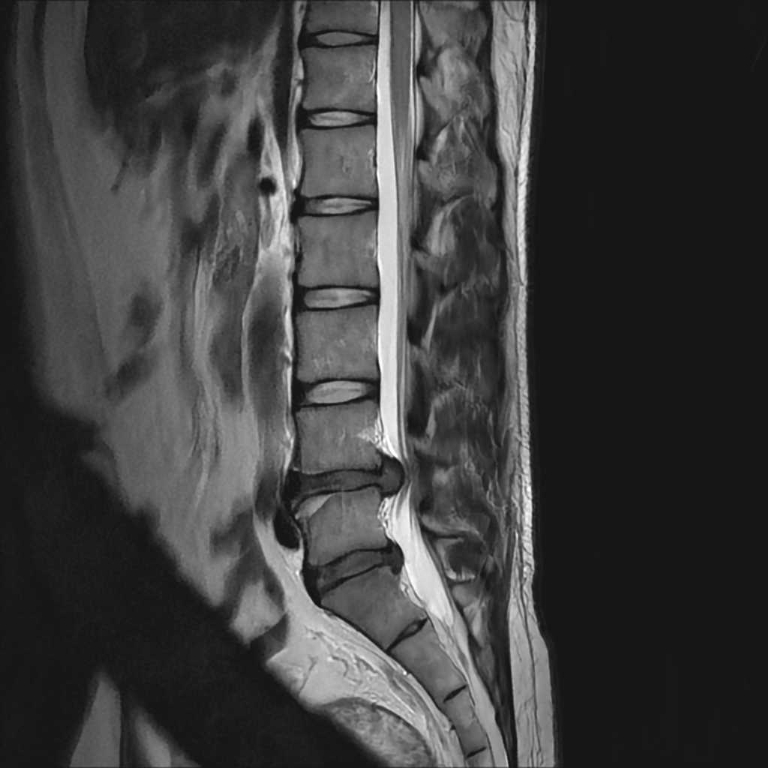

整形外科領域

脊椎

椎間板ヘルニア